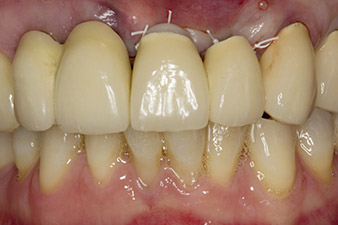

Following primary healing, the soft tissues were shaped using the basally lined bridge. Two months later the site was exposed by a slightly palatal alveolar ridge incision (Fig 2). The dimensions of the alveolar bone proved to be sufficient at position 22. Figures 2 and 4 show the preparation of the implant bed, the tapping and the implantation using Implantmed.